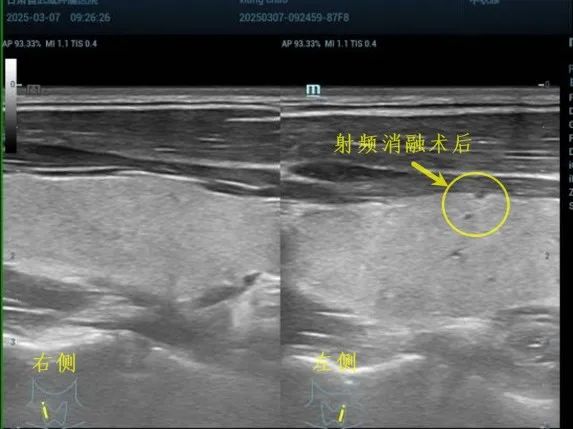

甲状腺结节射频消融

治疗前 治疗后6月